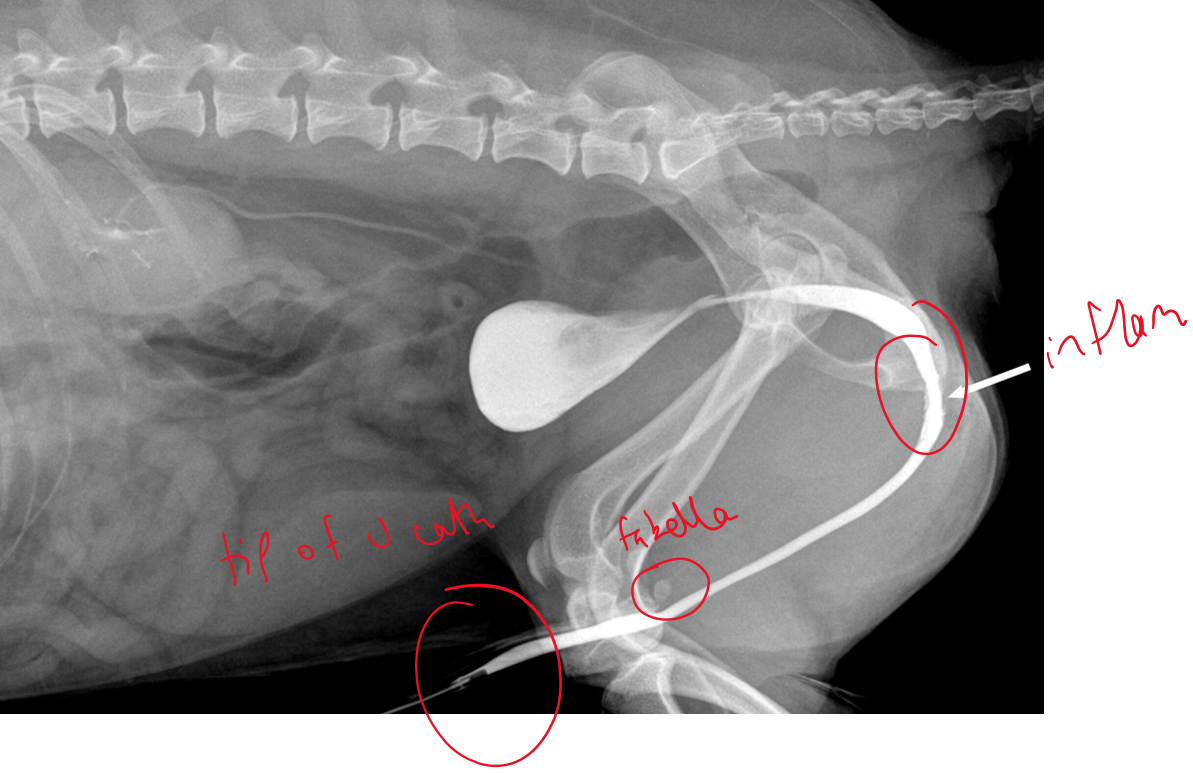

Describe this retrograde urethrography radiograph (dog)?

Membranous urethra is wider (normal)

Fabella of femur can look like caliculi so pull legs forward

No contrast leakage

What is being shown here?

RTA —> femoral #

Bladder rupture —> leakage of urine into the peripheral tissues

cannot see clear bladder outline

gas obacity in abdomen, consistent with ruptured ureter